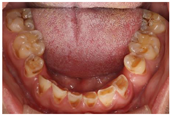

(1)面部检查:面部外形不对称,颏部居中,两侧口角高度不一致,面下1/3高度减小,两侧颧弓突度一致,下颌前突。中位笑线,上唇长度适中(图1)。(2)关节检查:颞颌关节:弹响(-),杂音(-),疼痛(-)。开口度正常,开口型有偏斜,肌肉触诊压痛:右侧上颌结节(+)、左侧上颌结节(++)、双侧翼内肌(+),其他肌肉及颞下颌关节区未诉异常,关节载荷实验无任何紧张和疼痛不适。(3)口内检查:上下颌牙中线较面中线向右偏斜,前后牙广泛不均匀磨耗,前牙磨耗后呈刃状;14、21、22、23及下颌牙唇颊侧颈部见釉质缺损,部分牙本质暴露,呈黄褐色,少量白垩色;44牙见开髓孔,表面暂封。12缺失,缺失牙间隙无。全口牙龈色形质未见异常,11牙、21牙唇侧牙龈龈缘高度不一致,21牙较11牙龈缘高约3mm。全口口腔卫生状况良好,菌斑、软垢少量,未及牙石及牙周袋。咬合检查:11-14牙与对颌牙反

,21牙与31、31牙对刃,左侧尖牙至前磨牙深覆盖,

曲线不平(图2,图3)。(4)影像学检查: